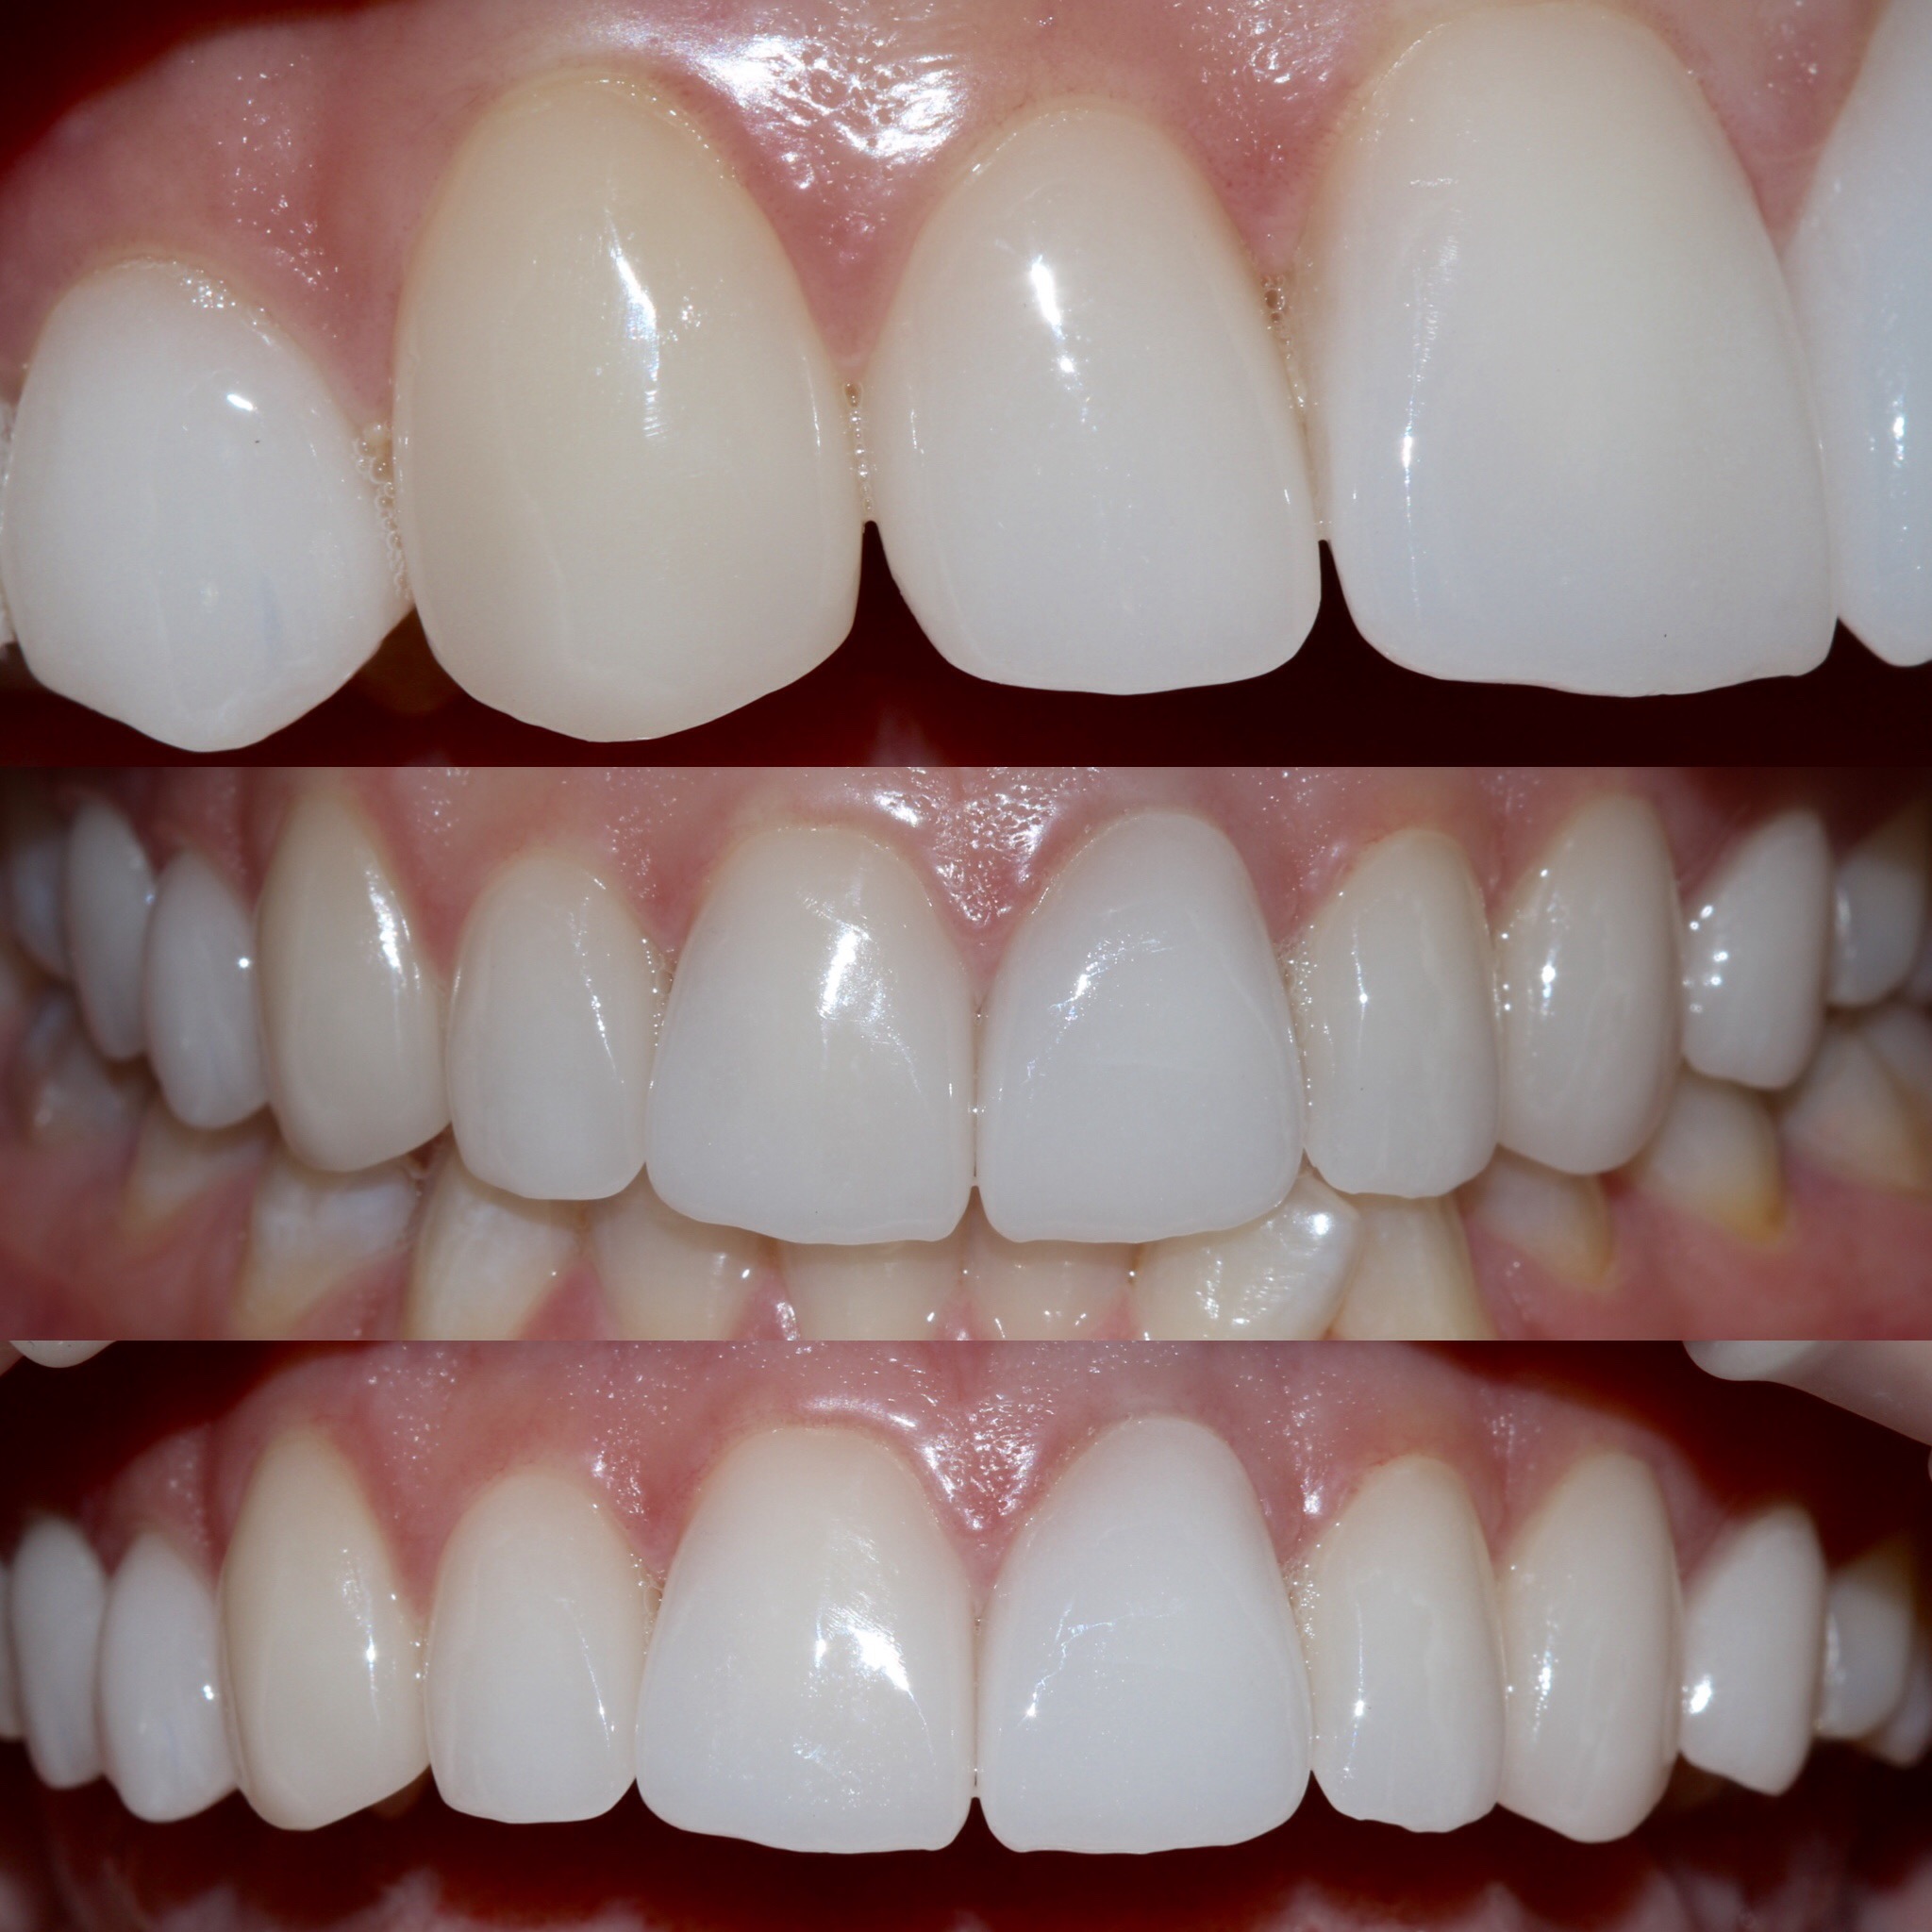

Патологическая стираемость, снижение прикуса . Как помочь?

- Остановить разрушительный процесс.

- Вернуть изначальный уровень высоты коронок.

- Заменить старые протезы, при необходимости.

- Адаптация к новому положению челюсти и ее работе.